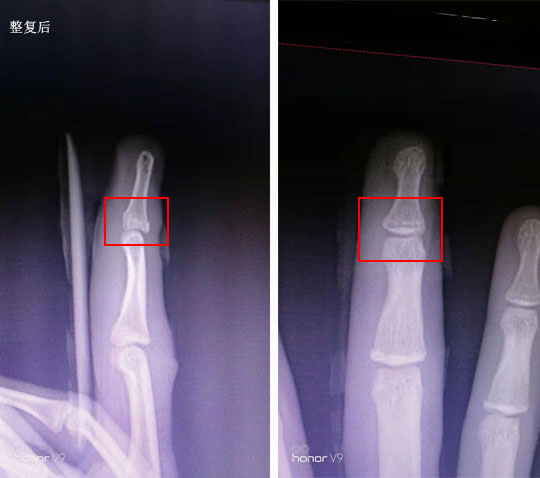

保守治疗指骨撕脱性骨折

指伸肌腱止点撕脱性骨折,手法复位,夹板固定。